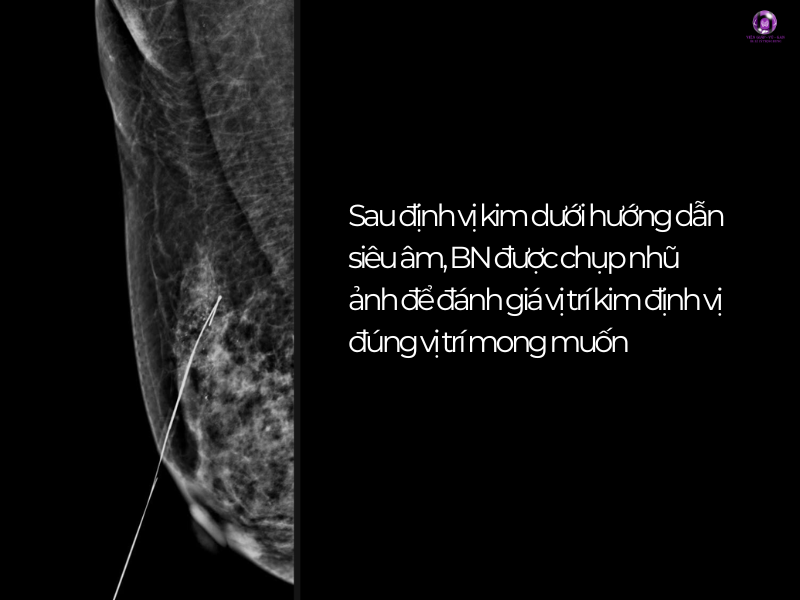

Xử lý ban đầu

- Định vị kim dưới hướng dẫn siêu âm vùng xáo trộn cấu trúc ¼ trên ngoài vú phải vị trí 8-9 giờ cách núm vú 5cm, tương ứng với mảng thay đổi sợi bọc trên siêu âm.

- Mổ sinh thiết + GPB vị trí tổn thương nghi ngờ nhất.